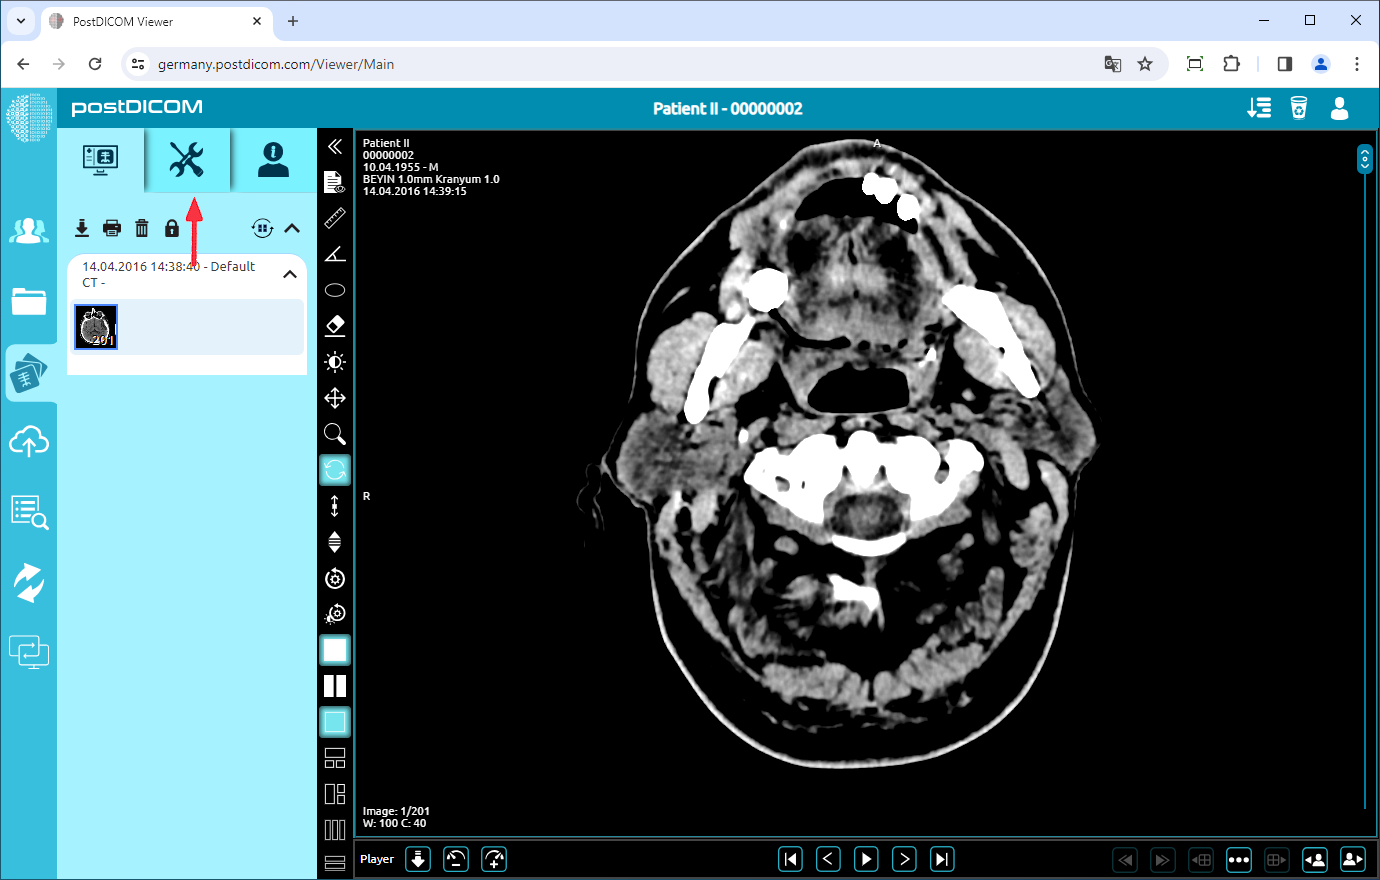

On the “Patient Search” page, all patient orders in your account will be displayed. Double-click on the order you want to view the images. The “View” page will be opened. Click on the “Tools” icon on the upper left side of the page.